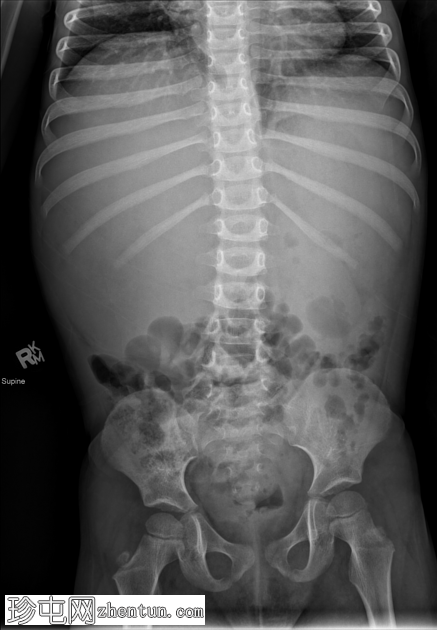

X线检查

腹部整体密度增高。肝脏轮廓显示不清。小肠袢向下移位。